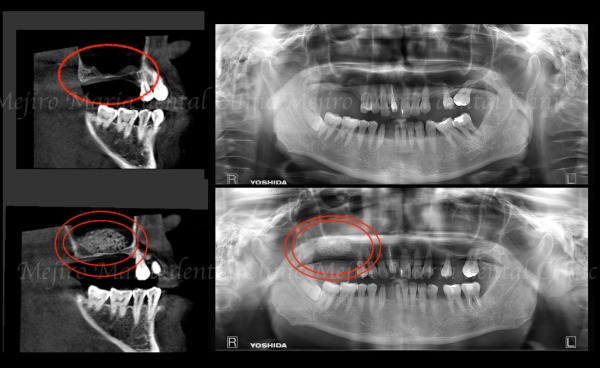

今回のように、重度の歯周病を患ってから抜歯をおこなった場合、抜歯後の歯周組織の喪失が著しくなります。特に上顎は上顎洞が近接しているため、インプラント埋入の骨量が不足することが多々見受けられます(画像赤丸○部分)。

インプラントは骨との結合(オッセオインテグレーション)によってはじめて力に耐えるため、骨が薄い、または喪失してしまった部位では、予知性が低下します。

上顎の骨量不足に対してはGBR・ソケットリフトの他に、今回のように比較的広範囲に骨が必要な症例では、サイナスリフト(上顎洞挙上術)を行うことで、インプラントを支える新たな骨を確保することができます。(外科画像1)

サイナスリフトでは、側方から上顎洞粘膜を挙上し、できた空間に人工骨を填入することで3〜6ヶ月後にインプラント埋入可能な骨が形成されます(赤二重丸◎部分)。